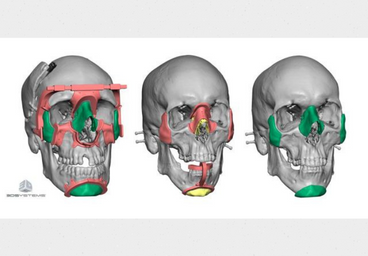

Experience the benefits of 3D printing in surgery with a personalized 3D printed model tailored to the patient's needs, assisting surgeons in achieving the best possible outcome for the surgery.

3D printing has revolutionized pre-surgical planning by providing doctors with accurate and detailed 3D models of patient anatomy. With 3D printing technology, doctors can now visualize complex structures and plan surgical procedures with greater accuracy and precision. This technology enables doctors to identify potential risks, explore different surgical options, and develop personalized treatment plans for each patient. 3D printing also helps to reduce surgery time and minimize the risk of complications, resulting in improved patient outcomes. With 3D printing, doctors can enhance their pre-surgical planning process, delivering better care to their patients.

While performing a surgical procedure, the stakes are high, and even a small error can have disastrous consequences. Therefore, it's crucial to be well-prepared for any unexpected challenges that may arise during the surgery. By taking the necessary precautions and having a detailed plan of action, surgeons can ensure the best possible outcome for their patients. In the world of life and death, preparedness is the key to success.

Our state-of-the-art surgical preparation service includes the use of advanced technology such as

3D printing to provide surgeons with accurate and detailed anatomical models. By using patient-specific

CT and MRI scans to create these models, surgeons can perform mock surgeries to plan and prepare for the

actual procedure. This process not only helps to avoid any potential surprises during surgery but also

boosts the surgeon's confidence and morale, knowing they have a comprehensive understanding of the

patient's anatomy. With our advanced preparation techniques, you can rest assured that your surgical

team is fully equipped to provide you with the best possible outcome.

Transforming surgical planning with customized 3D printed models, created from patient CT and MRI scans. Our cutting-edge 3D printing technologies, including FDM, SLS, and SLA, allow for precise and accurate replicas that provide invaluable preoperative and operative guidance for surgical teams. In addition, we provide virtual 3D models in multiple file formats, enabling further analysis and planning for optimal patient outcomes. Trust us to enhance your surgical precision and improve patient care with our advanced 3D printing solutions.

Revolutionize surgical precision with personalized 3D printed surgical guides, designed to minimize the risk of errors and ensure optimal accuracy. Our state-of-the-art 3D printing technologies, including FDM, SLS, and SLA, allow us to create customized surgical guides that fit each patient's unique anatomy and aid surgeons in achieving unparalleled precision, even in the absence of unexpected elements. Trust us to provide cutting-edge solutions that enhance your surgical outcomes and improve patient care.

Revolutionize surgical planning with real-time 3D virtual models, generated from patient CT and MRI scans. Our cutting-edge technology allows for visualization of the patient's case in real-time, providing invaluable insights for preoperative surgical planning. These 3D digital models can be exported in various file formats, enabling numerous applications for further analysis and planning. By improving the comfort and efficiency of your doctor/surgeon to comprehend and operate, our virtual 3D models enhance surgical precision and patient outcomes. Trust us to deliver innovative solutions that transform the way you approach surgery.